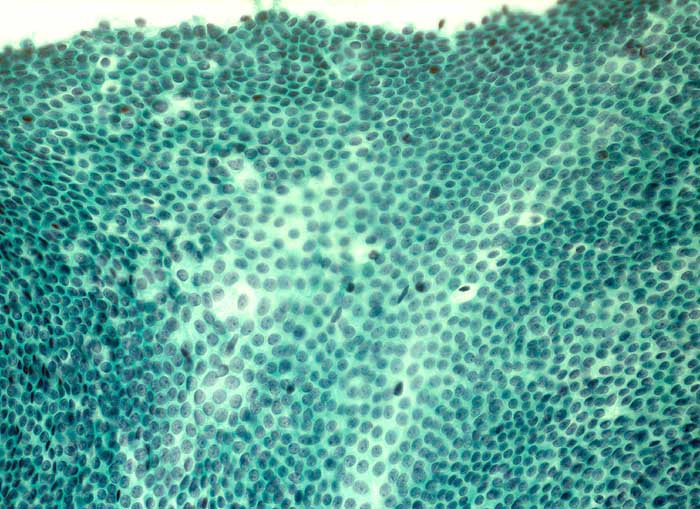

Das invasive Mammakarzinom zeigt zytologisch eine homogene Population maligner Zellen. Typischerweise sollten die Ausstriche zellreich sein und alle vorhandenen Zellen sollten maligne aussehen. Wenn man atypische Zellen suchen muss, ist der Ausstrich nicht diagnostisch für ein Karzinom, kann aber gleichwohl verdächtig sein. Die malignen Zellen sind in lockeren Gruppen gelagert und viele liegen einzeln. Crowding, Zellkannibalismus und Kernmolding sind gute Hinweise auf Malignität. Myoepithelien sind meistens aber nicht immer abwesend. Mammakarzinomzellen sind eher monomorph und deutlich grösser als normale duktale Epithelien. Zellkerne, die grösser sind als zwei Erythrozytendurchmesser, sind tumorverdächtig. Fast immer sind Kerbungen der Zellmembran nachweisbar. Das Chromatin ist im Gegensatz zu anderen Adenokarzinomen fein granulär und gleichmässig im Kern verteilt. Nukleolen sind meist unscheinbar. Makronukleolen sprechen für ein invasives Karzinom.

Die Kohäsivität ist das wichtigste Kriterium zur Feststellung des Differenzierungsgrades. Bei hoch differenzierten Karzinomen finden sich Verbände, bei wenig differenzierten liegen die Tumorzellen vermehrt einzeln. Wenig differenzierte Karzinome zeigen gesteigerte Kernatypien und der Hintergrund ist eher detritisch aufgrund ausgedehnter Tumornekrosen.

Unten werden Beispiele von einem hochdifferenzierten und einem wenig differenzierten Mammakarzinom gezeigt.